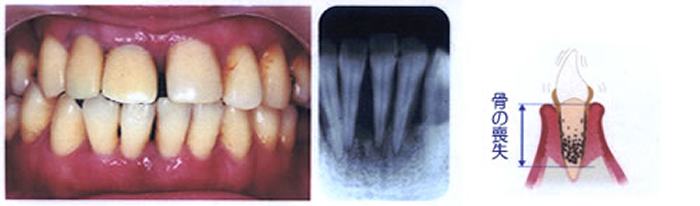

重度歯周炎

歯を支える骨がなくなってきて歯がぐらつき、このまま放っておくと歯が抜けてしまいます。

歯ぐきが下がる、膿がでるなどの症状もみられます。